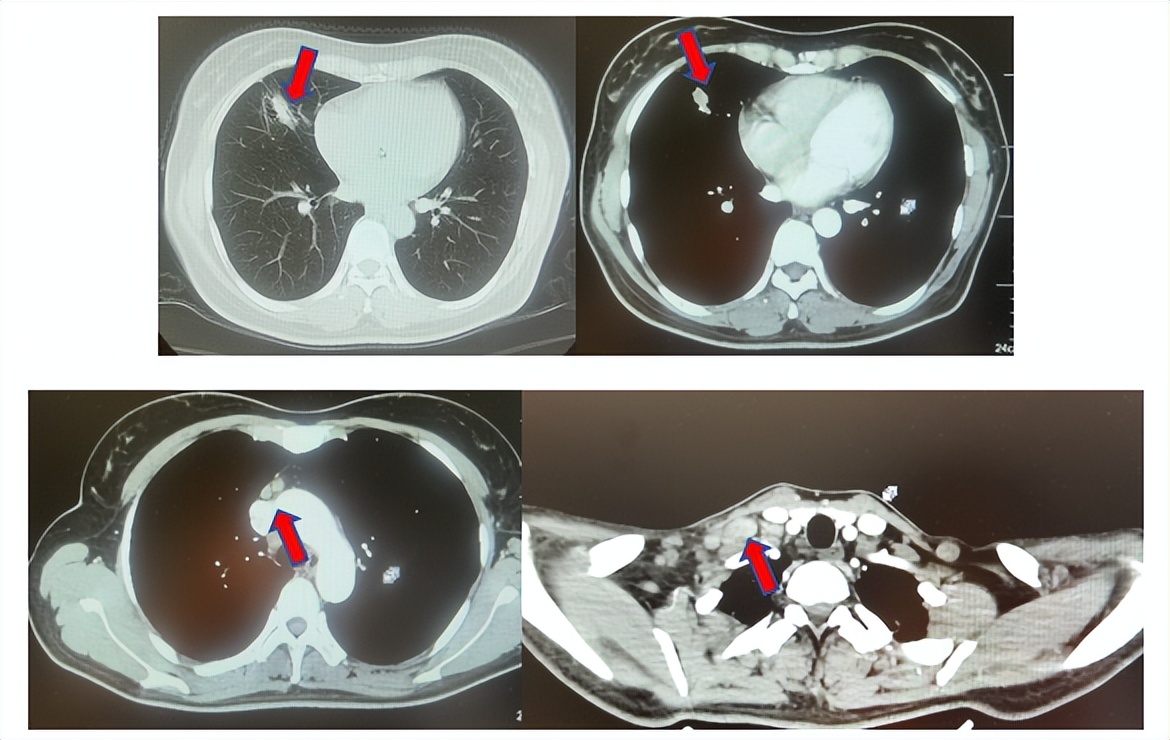

患者进入到二线治疗,该患者再次符合我科“优替德隆对照多西他赛治疗含铂化疗失败的局部晚期或转移性非小细胞肺癌的III期、开放、随机对照临床试验”经随机进入多西他赛组,截止至目前患者已行多西他赛治疗19周期,期间评效为SD(图3),二线无进展生存至今为14个月,患者总生存期截止目前超过92个月(整体治疗过程如图4所示)。

图3:上两图分别展示2024年1月患者一线进展时肺CT肺窗及纵隔窗肺内病灶影像,下两图表示2024年12月患者二线治疗间期评效时肺CT肺窗及纵隔窗肺内病灶影像